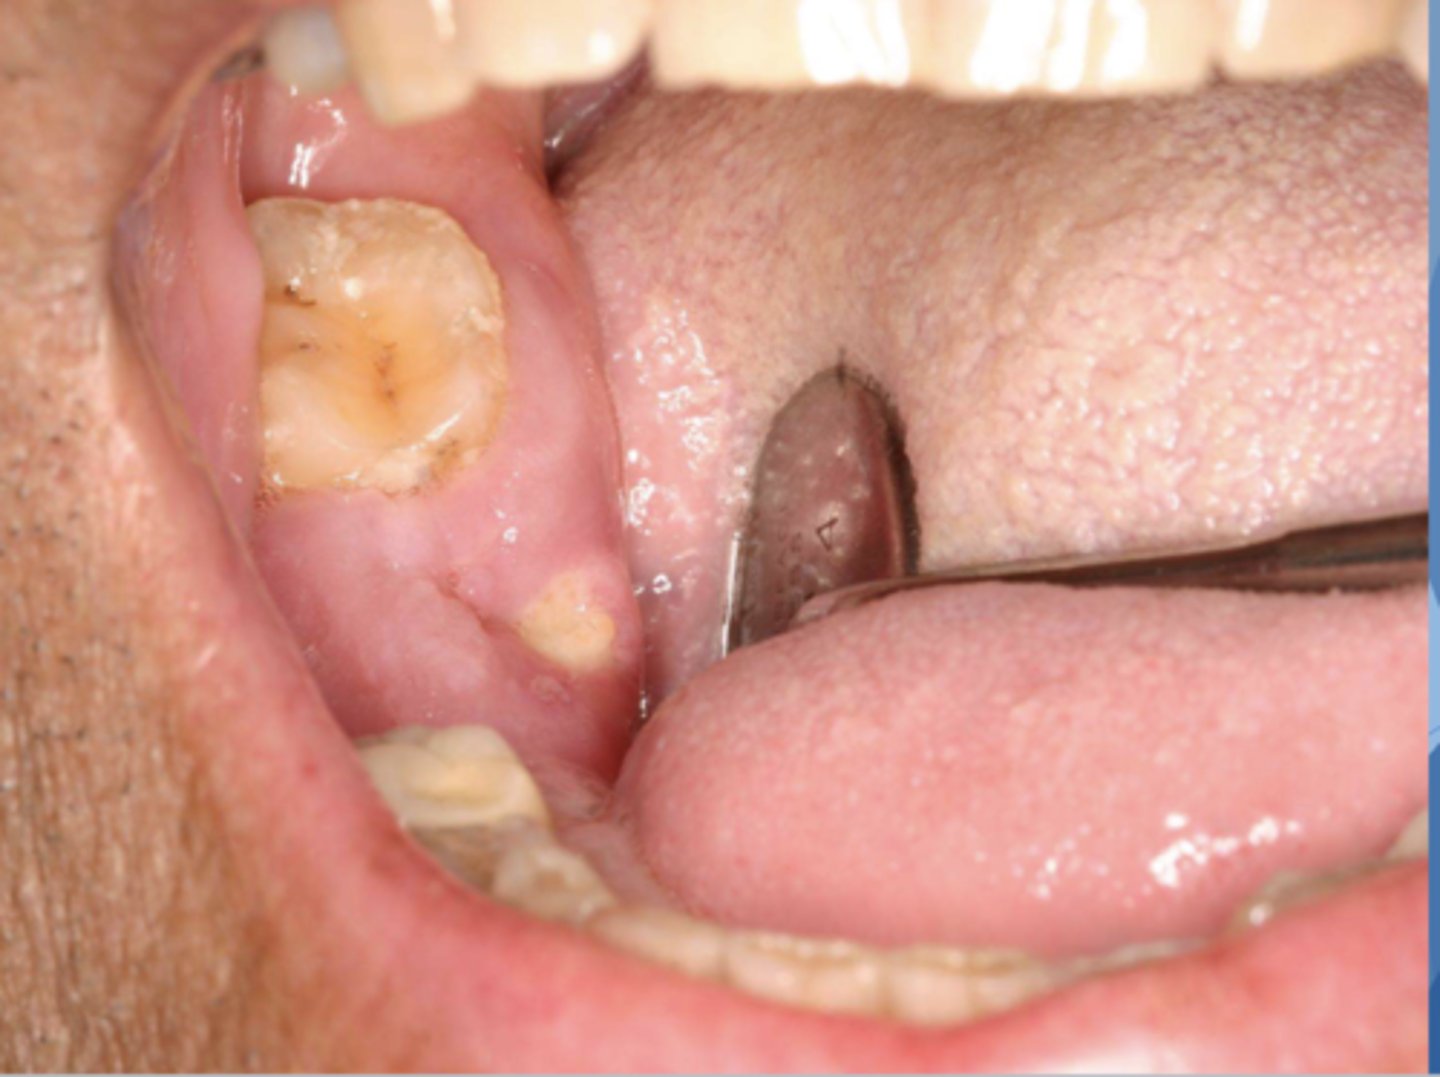

What do you suspect? Hint: Patient is taking Zometa to treat osteoporosis

MRONJ

Patient has multiple myeloma and is currently on chemotherapy and taking Flosamax (Alendronate). What do you suspect?

Upon clinical examination, you find a lesion that appears to be necrotic bone showing through the lingual attached gingiva of #31. What do you suspect? Is there anything you should look for in the patient history?

osteonecrosis/osteoradionecrosis/ MRONJ

*should see if patient is currently taking a bisphosphonate, undergoing head/neck radiation therapy, or on any other anti-resorptive or anti-angiogenic therapy

Patient was diagnosed with Paget's disease 6 mo ago and began anti-resorptive therapy upon diagnosis. What do you suspect this lesion is?